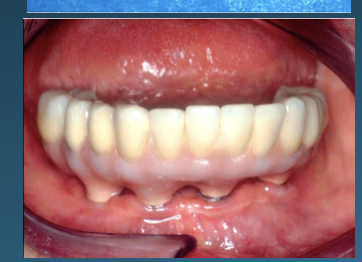

Patient Factors that May Contraindicate Fixed Implant-supported Prosthetics

(42.) Fixed-removable prosthesis.

Figure 42

(43.) Fixed-removable prosthesis.

Figure 43

(44.) Fixed-removable prosthesis.

Figure 44

(45.) Fixed-removable prosthesis.

Figure 45